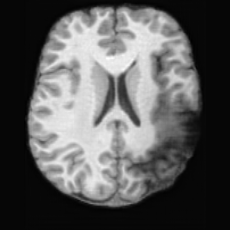

(a)PathologicalInput ImageSynthSR [18]Brain-ID [28]UNA [30]USBHealthyGround TruthRefer to captionRefer to captionRefer to captionRefer to captionRefer to captionRefer to captionRefer to captionRefer to captionRefer to captionRefer to captionRefer to captionRefer to captionRefer to captionRefer to captionRefer to captionRefer to captionRefer to captionRefer to captionRefer to captionRefer to captionRefer to captionRefer to captionRefer to captionRefer to caption(b)HealthyInput ImageConditionalLesion MaskUNA [30]USBRefer to captionRefer to captionRefer to captionRefer to captionRefer to captionRefer to captionRefer to captionRefer to captionRefer to captionRefer to captionRefer to captionRefer to captionRefer to captionRefer to captionRefer to captionRefer to caption

Figure 5: Comparison of bidirectional brain editing. (a) pathology-to-healthy, the circles and arrows highlight lesion regions and unsuccessful reconstructions; (b) healthy-to-pathology. Note that SynthSR and Brain-ID cannot perform healthy-to-pathology editing.

Pathology-to-Healthy Editing. Fig. 5 (a) presents comparison results on four input brain images with lesions of varying sizes, shapes, and densities. All competing models, although specialized for healthy brain image synthesis, struggle to reconstruct pathological regions, especially near lesion boundaries. In contrast, USB accurately reconstructs the corresponding healthy brain, even in challenging cases with large, high-density lesions where normal brain structures are almost completely obscured (last row). Tab. 2 provides a quantitative comparison for pathology-to-healthy editing, where USB achieves the best performance across all three datasets, demonstrating the effectiveness of its unified framework in reconstructing healthy brains from pathological inputs. Additional results are in Suppl. B.

Healthy-to-Pathology Editing. As shown in Fig. 5 (b), given a healthy brain image paired with a random lesion mask, USB seamlessly embeds the lesion into the healthy anatomy, producing realistic pathological appearances consistent with surrounding structural context. Yet UNA’s syntheses are visually unrealistic, with the conditioned lesion mask simply overlaid as a parallel layer onto the healthy brain. Tab. 3 further demonstrates USB’s superior performance. The evaluation was conducted on 100 pairs of lesion masks and healthy brains, with real stroke images